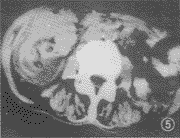

图5 结肠腺癌继发肠套叠,套叠头部肠壁局限性不规则肿块样增厚,符合肠癌特征